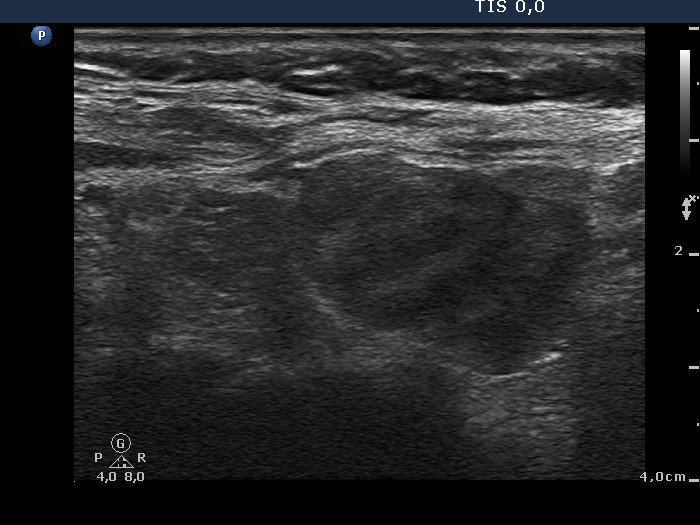

Lymphocytic thyroiditis - case 1441

Right lobe

Focal form of lymphocytic thyroiditis is presented. The thyroid has numerous discrete, hypoechoic lesions which correspond to more active foci of thyroiditis. The interpretation of the relatively large ventral hypoechoic area in the left lobe (right upper image can cause problem), however, longitudinal scan decides the issue: this field cannot be a pathological nodule.